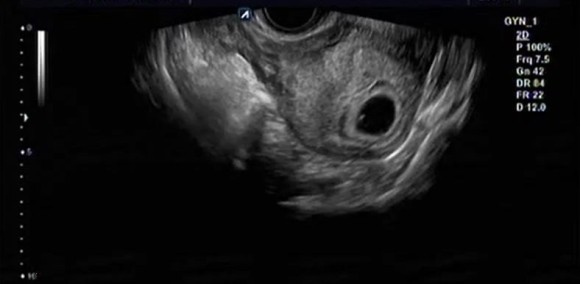

태아는 너무 작아 초음파 로 볼 수 없어요.